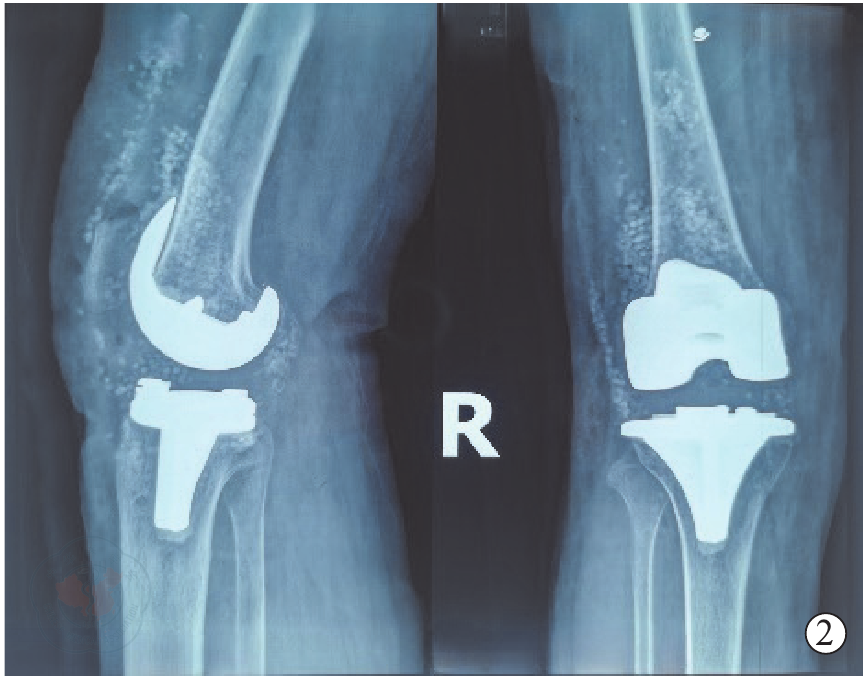

图2 术后第1天右膝正侧位X线片,示假体位置良好